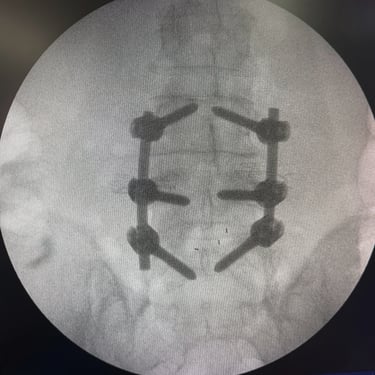

La inestabilidad de la columna lumbar ocurre cuando los segmentos vertebrales pierden su alineación y soporte normal, generando dolor lumbar crónico, limitación funcional y, en algunos casos, compresión de las raíces nerviosas. Cuando el tratamiento conservador no resulta efectivo, la fijación transpedicular (FTP) asociada a la fusión intersomática transforaminal (TLIF) representa una alternativa quirúrgica eficaz. Este procedimiento permite estabilizar el segmento afectado, descomprimir las estructuras nerviosas y restaurar la biomecánica de la columna. La combinación de fijación y fusión reduce el dolor, mejora la estabilidad vertebral y favorece una recuperación funcional segura y progresiva.